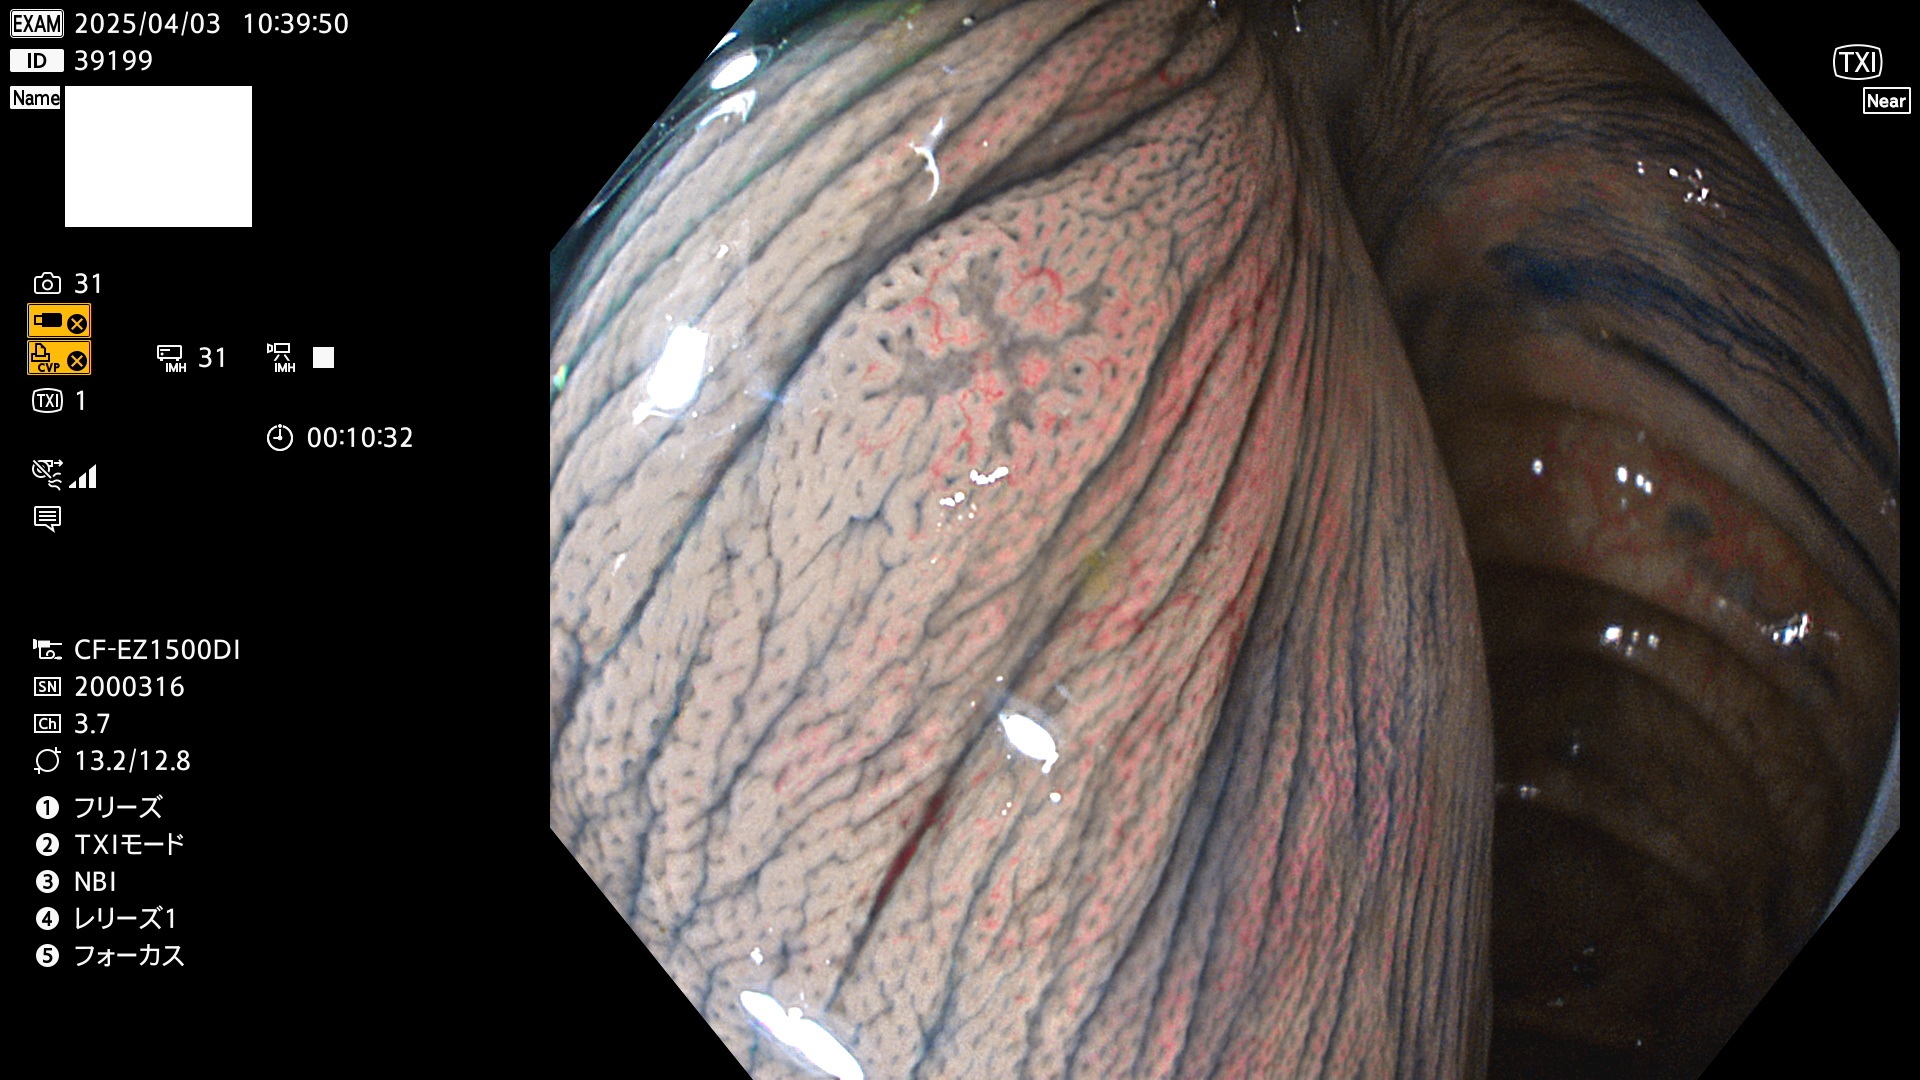

今週のUb、Uc型腺腫

完全に平坦な物をUb、陥凹している物をUcと呼びます。Ubは認識が困難で、Ucはびらん(炎症)と紛らわしいために見落とされやすく、「内視鏡後・大腸癌」の原因になります。

抽出の対象期間 2025年4月3日〜4月6日の4日間(48件の検査)4個 (4/48=8%)